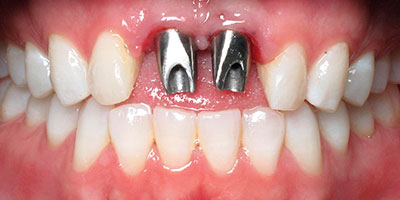

Se realiza tomografía e imagen tridimensional 3D, observamos además de la lesión traumática, que la paciente tiene raíces enanas.

Decidimos: bajo anestesia local. previa asepsia y antisepsia, la limpieza de los alvéolos y la colocación de paralelos e implantes dentales.se colocan sus mismas coronas naturales para darle forma a los tejidos blandos y conservar papilas anatómicas.

Rx Panoramica Post Quirúrgica

Coronas Provisionales Inmediatas